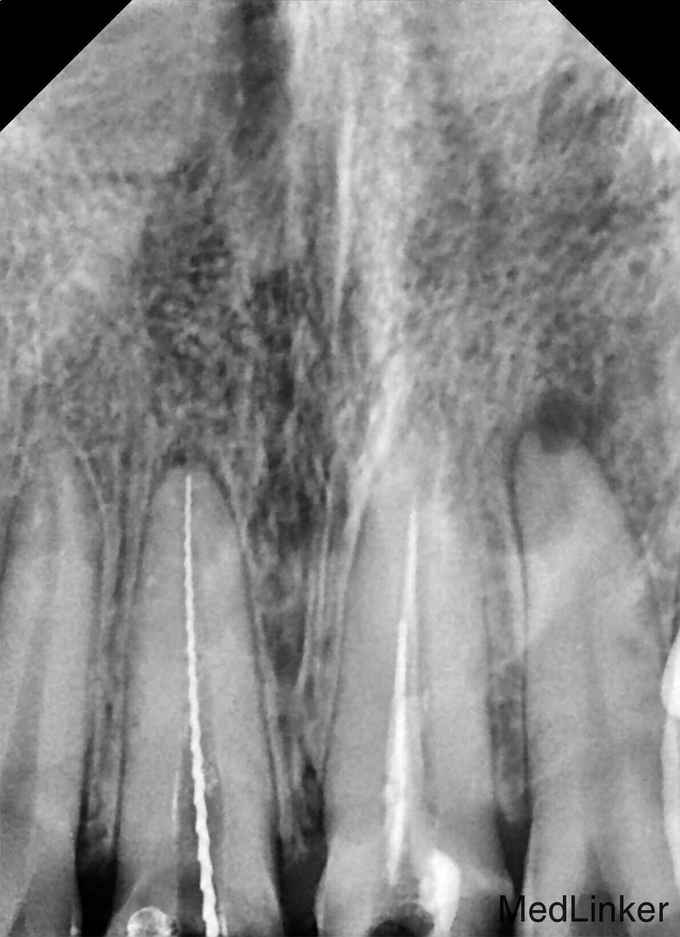

检查:11牙、21牙烤瓷联冠,大面积崩瓷,松(-),22牙体变色 X片示11牙、21牙根管欠填,根尖暗影,22牙根尖暗影

诊断:11牙、21牙欠填,慢性根尖周炎;22牙慢性根尖周炎 治疗:11牙、21牙拆冠,H锉配合超声去除牙胶尖,扩锉根管至70#,示踪,修尖,充填;22牙根管治疗;11-22牙分别行纤维桩+树脂核+全瓷冠修复